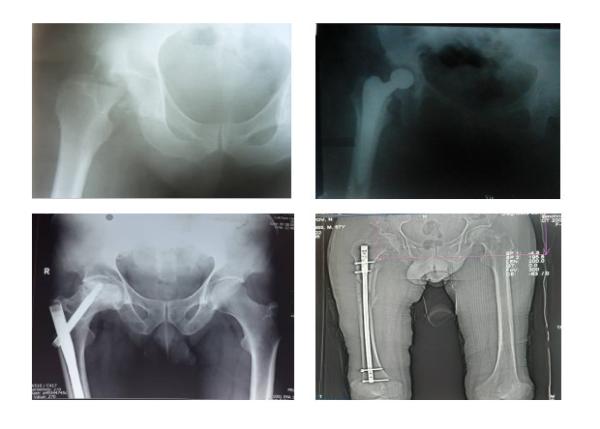

Кандидат медицинских наук Таджикистана Давронджон Махмудов представил доклад «Оптимизация профилактики венозных тромбоэмболических осложнений — при проблемах длинных костей нижней конечности».

Как он отметил в своем докладе, венозные тромбоэмболические осложнения, к котором относятся тромбоэмболия лёгочной артерии, тромбоз глубоких вен, тромбофлебит подкожных вен, являются одной из наиболее актуальных проблем современной медицины.

По данным ВОЗ, ромбоэмболия лёгочной артерии явилась непосредственной причиной смерти каждого четвёртого умершего больного с повреждениями опорной двигательного аппарата и среди них преобладают пациенты с травмами бедра, таза, костей голени и сочетанные травм.

При этом, докладчик отмечает, что точная своевременная диагностика тромбоза глубоких вен на основе клинических симптомов затруднена, а применение дополнительных методов исследования не всегда возможно. Подавляющее большинство случаев тромбоза глубоких вен в посттравматическом и послеоперационном периодах не имеют ярких клинических проявлений. Поэтому, учитывая данные исследований, с практической точки зрения можно считать, что развитие тромбоза глубоких вен в дистальных отделах голени при повреждениях и оперативном лечении нижних конечностей, таза, сочетанной травме и постельном режиме больного, является закономерностью.